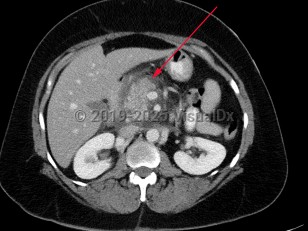

Acute pancreatitis is an acute inflammatory process of the pancreas characterized by the sudden onset of severe abdominal pain, most commonly epigastric in location, often with associated radiation of pain to the back. Nausea and vomiting are common associated symptoms.

Patients often present in distress, with associated tachycardia, tachypnea, and constant, rapid-onset abdominal pain, most commonly reported as midline epigastric abdominal tenderness. Nausea and vomiting are often reported as well. Patients with developing necrotizing pancreatitis may note fevers and chills.